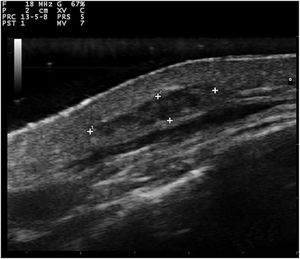

Exames de US Doppler colorido e em escala de cinza do nódulo subcutâneo e de uma das pápulas localizadas na região periareolar direita (fig. 1) foram realizados com um scanner MyLab25Gold equipado com um transdutor de matriz linear de 10‐18MHz (Esaote, Gênova, Itália). A US de alta frequência do nódulo malar subcutâneo revelou uma massa mal definida, alongada, heterogênea e hipoecoica localizada na derme profunda e hipoderme (fig. 2). Por outro lado, a US da pápula periareolar direita mostrou uma lesão bem definida, redonda, homogênea e hipoecoica localizada na derme superficial com elevação da epiderme (fig. 3). A US com Doppler colorido e direcional não mostrou aumento da vascularização em nenhuma das duas lesões. A histopatología de duas pápulas do tronco removidas cirurgicamente confirmou o diagnóstico de mixomas cutâneos (fig. 4). A lesão malar não foi excisada por razões estéticas.

Enquanto mixomas cardíacos se apresentam na US como massas pedunculadas, atriais e hiperecogênicas, a US de mixomas cutâneos ainda não foi descrita na literatura. Observamos que eles apresentam características ecográficas diferentes, dependendo de sua localização na pele. Os mixomas superficiais apresentam‐se como lesões bem definidas, arredondadas, homogêneas e hipoecoicas, localizadas na derme superficial com elevação da epiderme. Por sua vez, os mixomas subcutâneos aparecem como massas mal definidas, alongadas, heterogêneas e hipoecoicas, localizadas na derme profunda e na hipoderme. O diagnóstico diferencial ultrassonográfico dos mixomas superficiais deve ser feito com os tumores benignos da pele, como cistos, dermatofibromas, pilomatricomas e neurofibromas. Os cistos são lesões bem definidas, arredondadas, hipoecoicas ou anecoicas e geralmente apresentam realce posterior e sombreamento bilateral nas bordas. Os dermatofibromas são lesões mal definidas, hipoecoicas e heterogêneas. Na US, os pilomatricomas aparecem como lesões hipoecoicas com margens bem definidas e tipicamente apresentam pequenas calcificações múltiplas e sombreamento posterior. A US com Doppler colorido geralmente revela uma única artéria que penetra na lesão e dá origem a vários ramos intralesionais.7 Os neurofibromas são lesões hipoecoicas arredondadas, ovaladas ou fusiformes, que podem apresentar conexão com os feixes neurais aferentes e eferentes hipoecoicos. Por outro lado, o diagnóstico diferencial ultrassonográfico dos mixomas subcutâneos deve ser realizado com lesões mais profundas, como abscessos ou lipomas. Na US, os abscessos aparecem como coleções heterogêneas de fluido, com margens irregulares e aumento do fluxo vascular na US com Doppler colorido, em caso de inflamação ativa. Os lipomas são geralmente massas ovoides, hipoecoicas, subcutâneas, com linhas horizontais hiperecoicas lineares dentro da lesão.